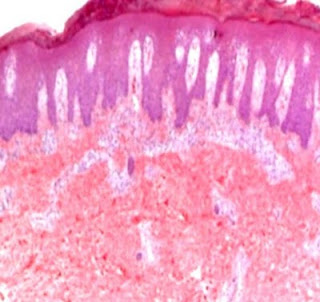

Answer of Dermatopathology Case 85

Graft-Versus-Host Disease Visit: Dermatopathology site Visit: Cutaneous Lesions in Graft versus Host Disease Abstract: Clinicopathologic characteristics of cutaneous chronic graft-versus-host diseases: a retrospective study in Korean patients. Int J Dermatol. 2010 Dec;49(12):1386-92. BACKGROUND: Chronic graft-versus-host disease (cGVHD) is a major complication in long-term survivors of hematopoietic stem cell transplantation (HSCT). Cutaneous manifestations are frequently the presenting features; therefore, the dermatologist needs to be aware of the wide spectrum of cutaneous cGVHD. METHODS: We retrospectively evaluated patients' characteristics, clinical, and histological features of cutaneous cGVHD and analyzed factors influencing the severity of cutaneous cGVHD in 100 Korean HSCT recipients between January 1, 1995, and December 31, 2007. RESULTS: Clinical manifestations of cutaneous cGVHD mainly presented as lichenoid (60.0%), sclerodermoid (12.0%), or erythematous maculopapul...

Dermatopathology Case 85

Image1 Image2 Image3 Case 85 A 35 year old male with skin lesions. Patient has a history of hematopoietic stem cell transplantation. Diagnosis